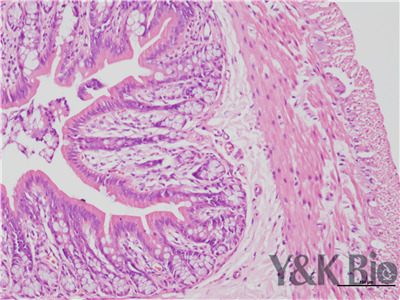

HE染色流程是什么,很多人都不知道,今天跟着小编一起来学习一下,切片的好坏直接影响疾病诊断的及时与准确性。因此一张高质量的HE染色切片,是实验室必须掌握的技术之一。HE染色目前在国内国外病理诊断上被

广泛采用,常规的染色方法。下面一起来看HE染色的基本顺序。一般切片的片子应在60-70度左右的烤箱中烘烤30分钟以才可以进行染色。总的来说是一个时间较长的过程。

1.样品制备

对于贴壁生长细胞,胰酶消化,调整细胞浓度约1×105/ml,滴加于盖玻片上(置于6孔板中),培养相应时间后,取出细胞爬片,用PBS 洗涤3次。2.样品固定 95%乙醇固定20min,PBS洗涤2次,每次1min。3.染核 苏木

素染液染色2-3min,自来水洗涤。4.分色 镜下观察,若细胞核染色过深,用1%盐酸酒精溶液分色数秒,自来水洗涤。 5.染胞质 浸入伊红染液染色1min,自来水洗涤。6.封片 吹干或自然晾干细胞爬片后,新疆中性树胶封片。

以上六点就是HE染色的基本步骤,大家可以参考一下哦 。